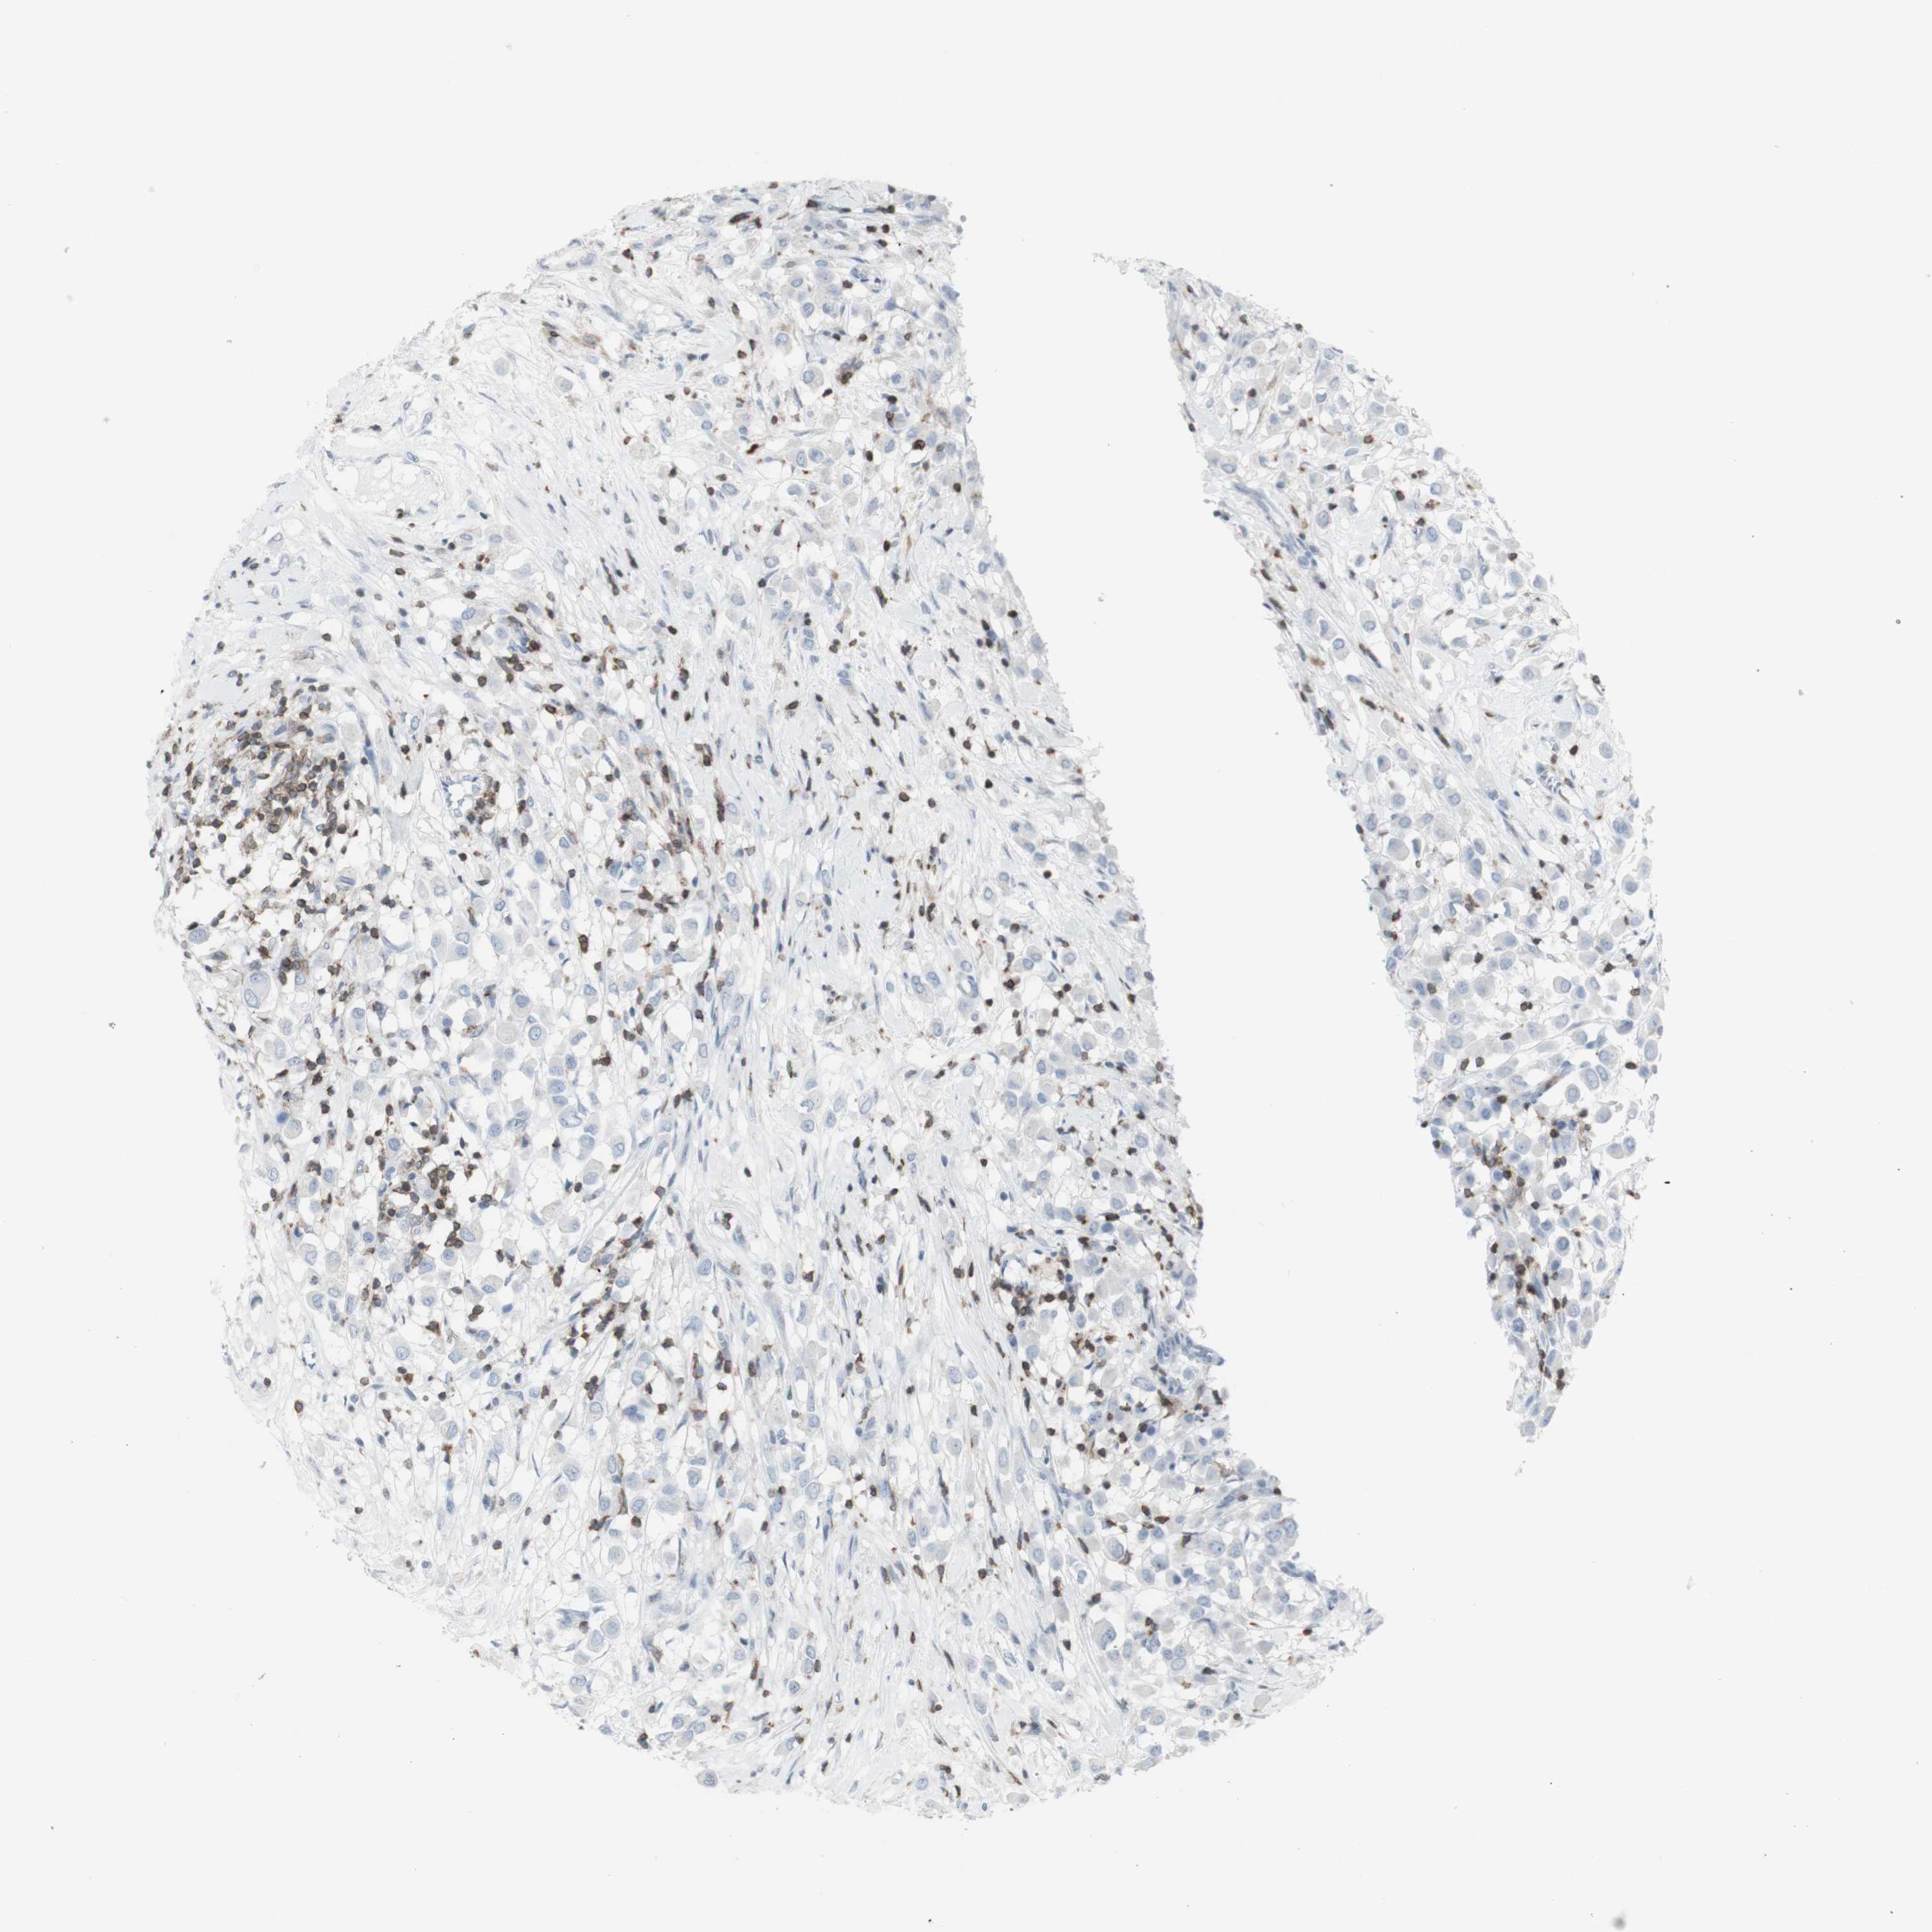

CANCER BREAST CANCER Show tissue menu

BRCA TCGA BRCA VALIDATION PROTEIN EXPRESSION

NRG1 is not prognostic in Breast Invasive Carcinoma (TCGA)

Average pTPM 2.5

Number of samples 1022